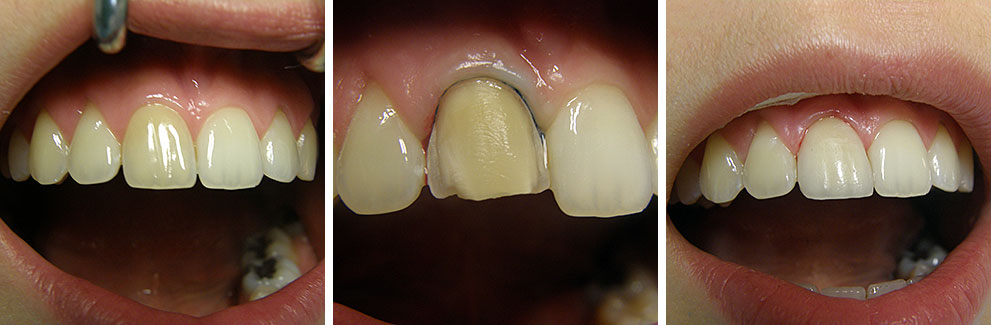

Estetska dentalna medicina